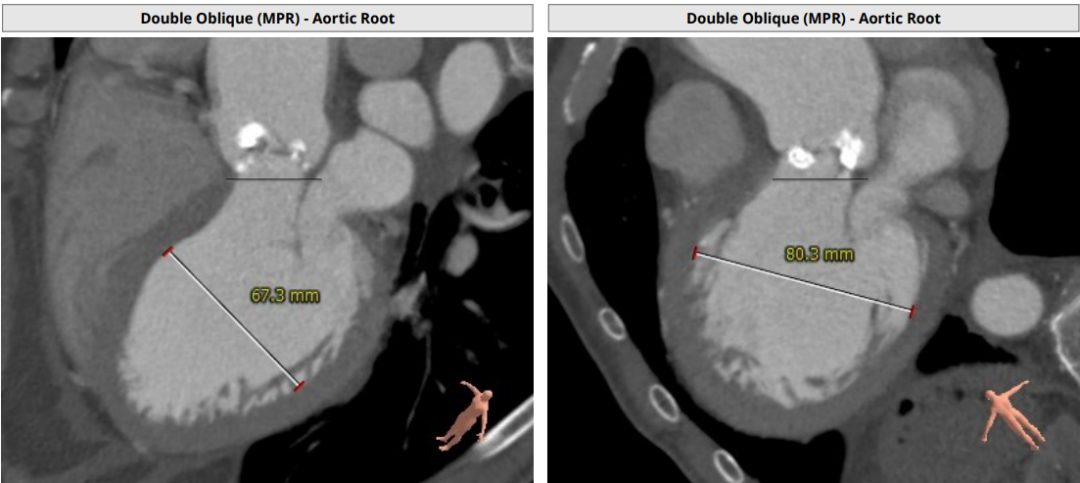

术前CT评估

Annulus Dimensions—27.4mm

LVOT—31.1mm

窦部:28*43.1mm

STJ—39.5mm

升主最宽处:50.5mm

路入分析:右股动脉

患者为Type0型二叶瓣,瓣叶明显增厚,极重度钙化,法式窦结构不大,双冠高度可,初步判断冠脉风险低,升主动脉明显增宽,左室肥大,EF值只有24%,心衰指征明显术中存在循环崩溃的可能;主动脉弓部走行较平缓,推荐右侧股动脉做为主入路。